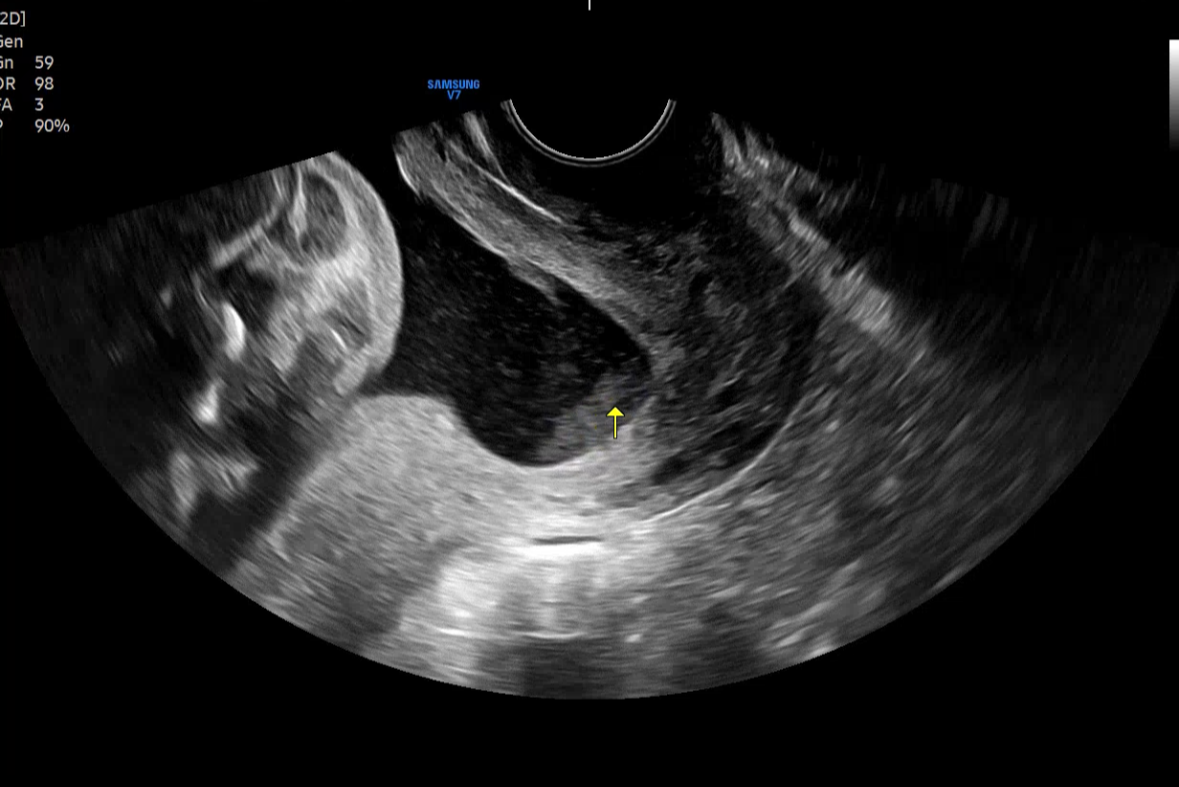

진료실로 이동해서 초음파를 보며 경과를 확인하셨다.

의사 선생님의 말을 정리하자면

수술은 잘 되었다.

양수 파수가 된 것 같은데

수술 후 바로 그런 게 아니고

몇 시간 있다가 그런 거라서 수술 때문은 아니다.

양수 검사 결과 양수 감염이 있다.

현재 아기는 괜찮다.

내일까지 지켜보자.